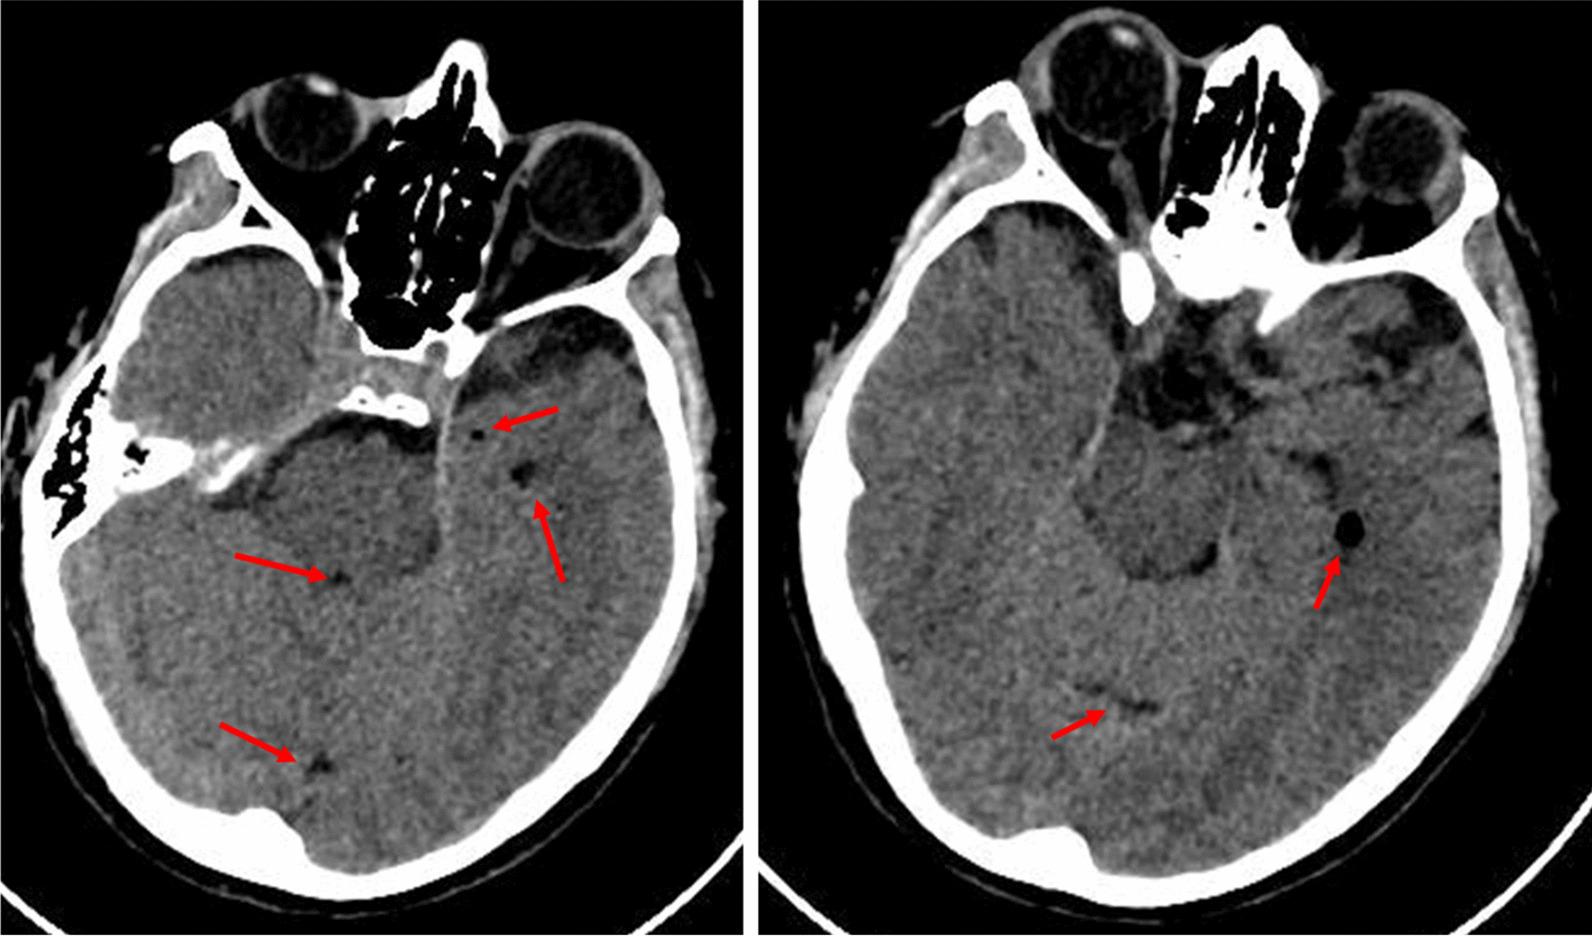

A 42-year-old Caucasian woman, with no relevant past medical history, received a lumbar paravertebral injection of lidocaine, thiocolchicoside, and L-acetylcarnitine for persistent low back pain. Approximately 30 minutes after injection, she experienced quick neurological worsening. Upon arrival at the Emergency Department, she was comatose, with fixed bilateral mydriasis, trismus, and mixed acidosis; seizures ensued in the first hours; slow progressive amelioration was observed by day 6; retrograde amnesia was the only clinical relevant remaining symptom by 6 months.

一名 42 岁的白人女性,无相关既往病史,因持续性腰痛接受了腰椎旁注射利多卡因、硫代秋水仙碱和左旋乙酰肉碱。注射后约 30 分钟,她出现快速神经恶化。到达急诊部时,她处于昏迷状态,双侧瞳孔固定,出现牙关紧闭和混合性酸中毒;随后出现癫痫发作;在第 6 天观察到缓慢的逐渐改善;6 个月时,仅遗留逆行性遗忘为唯一相关的临床症状。